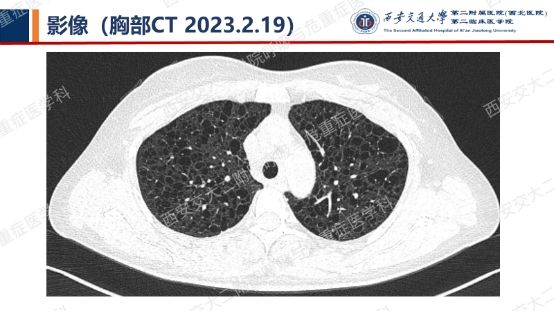

阅影探案,析病寻踪 // 第一期(上)

影像方寸藏玄机,同影异病辨真章。让我们一起抽丝剥茧,揭秘医学真相,解锁临床那些有意思的病例谜题吧!

结合以上患者病史及胸部CT,第一诊断分别考虑???欲知答案,且看后期!!!